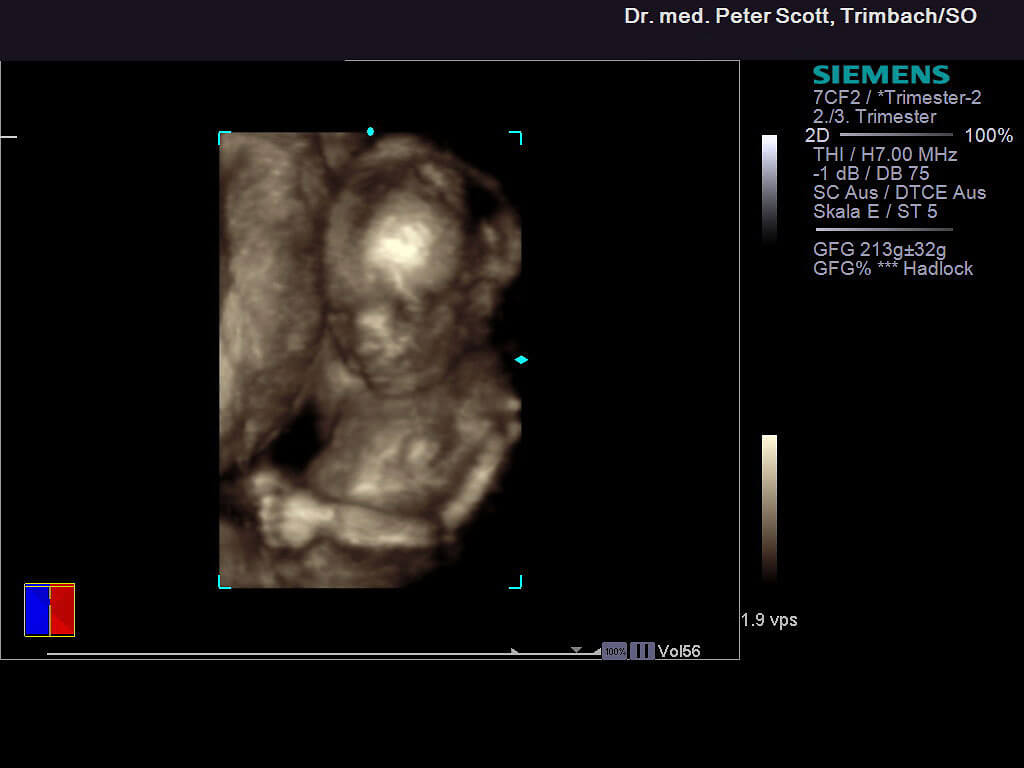

4 D Ultraschall

• Ergänzende Untersuchung, wirklichkeitsnahe dreidimensionale Bilder

• Benötigt gute Bedingungen (ideale Lage des Kindes, Fruchtwassermenge)

• Bringt meist keine zusätzliche Information (z.B. Missbildungen)